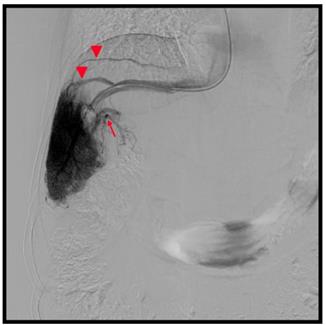

The presence of VVC was more frequent in patients with HVPG < 10 mmHg (10/18, 55.6 %) than in those with HGPV ≥ 10 mmHg (19/92, 20.7%; p = 0.0021) (Figure 1). The HVPG was lower in patients with VVC (n = 29; 12.6 ± 5.6 mmHg, 2.9-24.3) than in those without VVC (n = 81; 15.3 ± 4.3 mmHg, 7.4-30.3; p = 0.009). However, there was no difference in the incidence of extrahepatic portosystemic shunt between the two HVPG-related groups (5/18 vs. 30/92; p = 0.69).

53-year old male, hepatitis C related cirrhosis. Hepatic venography showed hepatic veins (arrow heads) demonstrated via venous-venous communications. The hepatic venous pressure gradient was 9.6 mmHg. (Arrow, intrahepatic portal vein)